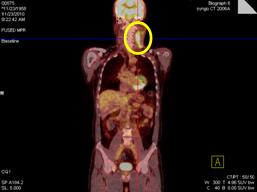

• Chụp PET/CT đánh giá toàn thân trước điều trị: Hình ảnh khối hạch vùng cổ trái kích thước 10x12 cm, tăng hấp thu FDG mạnh. Cơ quan bộ phận khác không thấy tăng hấp thu FDG.

• Hình 1: Hình ảnh khối hạch vùng cổ trái kích thước 10x12 cm, tăng hấp thu FDG mạnh (vòng tròn vàng).